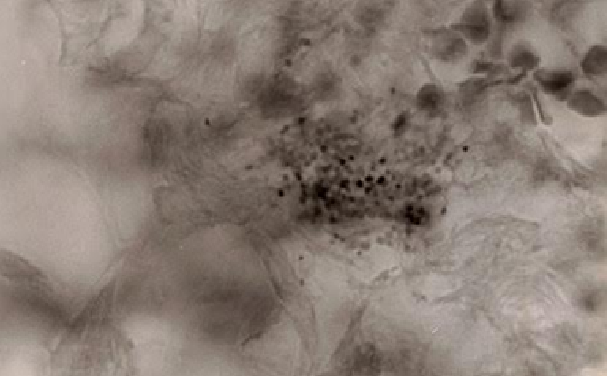

Figure 2. Tissue section of prostate cancer showing intracellular coccoid forms within the stroma. Fite stain, x1000, in oil.

The microbe appears both within cells (intracellular) and outside the cell (extracellular), scattered about the tissue.

With the highest magnification of the light microscope (1000 times) and with the oil immersion lens, the germ most commonly appears as the tiniest of barely visible round granular forms, or as larger round coccoid forms roughly the size of ordinary staphylococci.

Figures 1, 2, and 5 show examples of pleomorphic cancer bacteria in breast cancer, and prostate cancer, and AIDS-related Kaposi’s sarcoma.